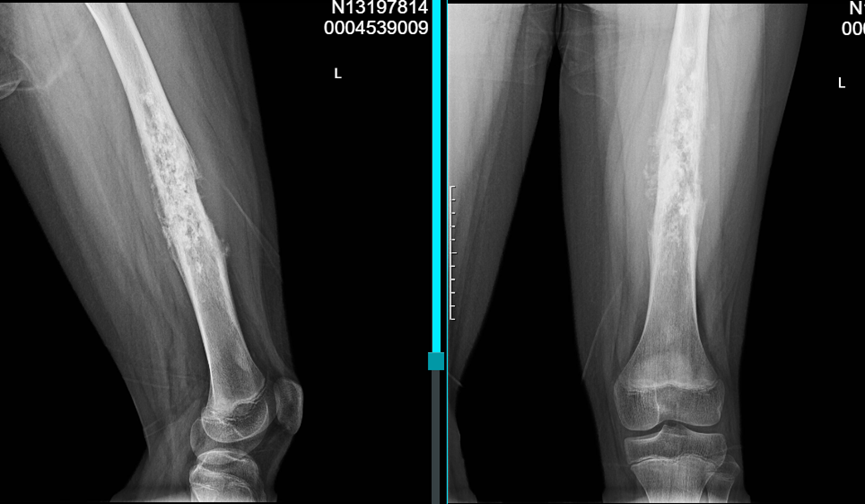

• X线:左侧股骨中段至干骺端混合性骨质破坏,伴日光放射状骨膜反应和Codman三角

• MRI:肿瘤范围约24cm,突破骨皮质,软组织肿块明显但未明显侵犯神经血管束